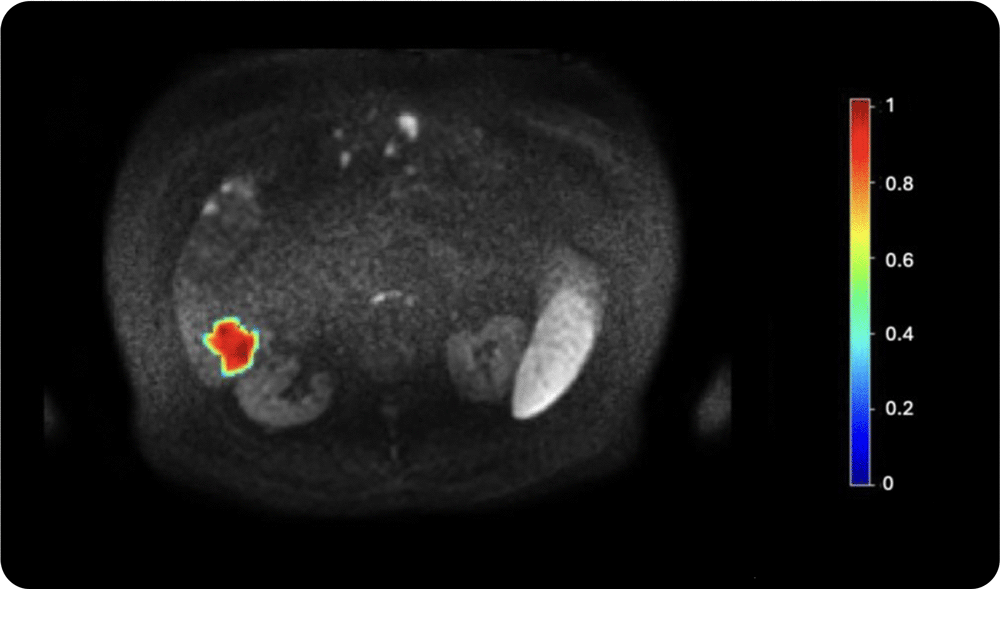

4. Tumor heterogeneity assessment

Entropy and other advanced radiomic features extracted from medical images help quantify intra-lesion variability; crucial for understanding tumor aggressiveness and predicting treatment response.

Intra-lesion heterogeneity quantified using entropy from a DWI MRI scan. Texture features reveal microscopic heterogeneity beyond visual assessment. High entropy often indicates more aggressive tumors, while low entropy suggests better treatment response. Temporal changes may serve as early biomarkers of therapeutic effect.